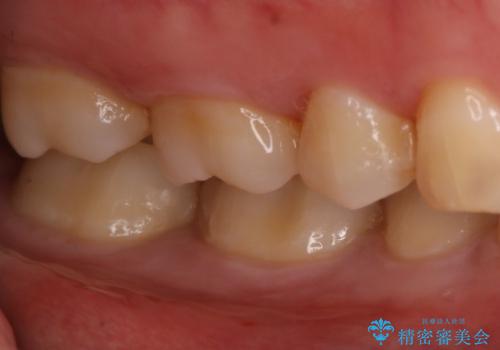

- 右下奥歯の虫歯治療を希望された患者様です。

保険の材料が劣化し、直下で虫歯の存在が確認出来ました。

セラミックを希望されたので形態・切削量を考慮し、セラミックインレーでの治療を計画しました。

虫歯が広く進行していましたが神経には到達していなかったので、予定通りセラミックインレーでの治療を行いました。